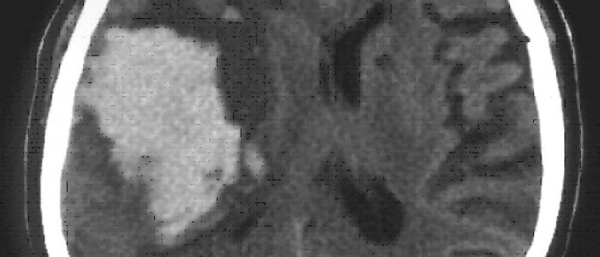

Во время диагностики ангиом следует проанализировать наличие симптомов, факторов и риска и уделить внимание семейной предрасположенности к онкозаболеваниям. Зачастую ангиома сосудов мозга — случайная находка во время компьютерной томографии (КТ). Этот метод неинвазивен, но не специфичен и значим только для опухоли большого размера.

Подтверждается диагноз гемангиомы мозга на основе аппаратного обследования – КТ или МРТ черепа.

МРТ (магнитно-резонансная томография) служит методом выбора для диагностики данной патологии, так как он гарантирует стопроцентную точность.